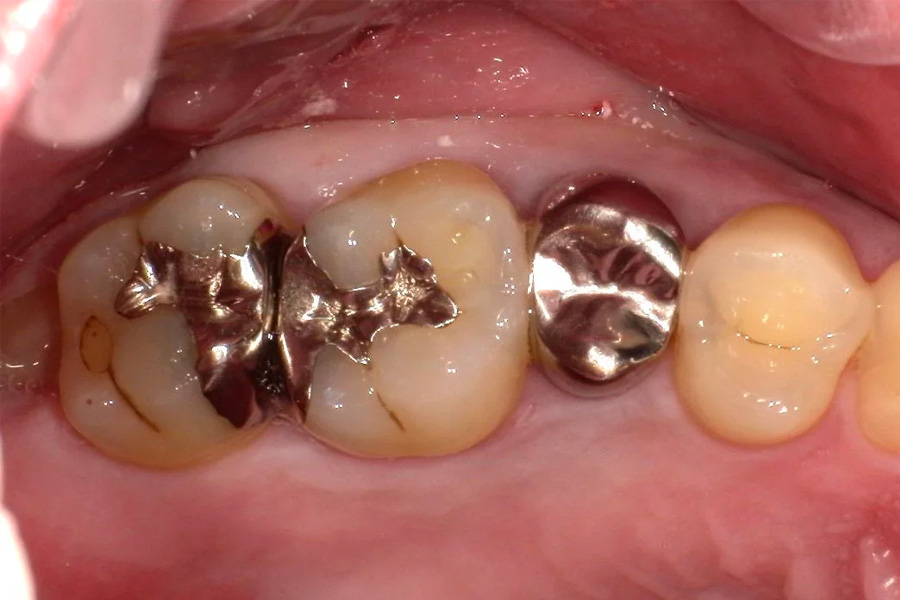

精密検査

実際にお口の中の状態をチェックしていきます。レントゲン撮影にて歯や骨の検査を行い、虫歯や治療痕のチェック、歯周病検査などの各種検査を行い、総合的な診断を下します。